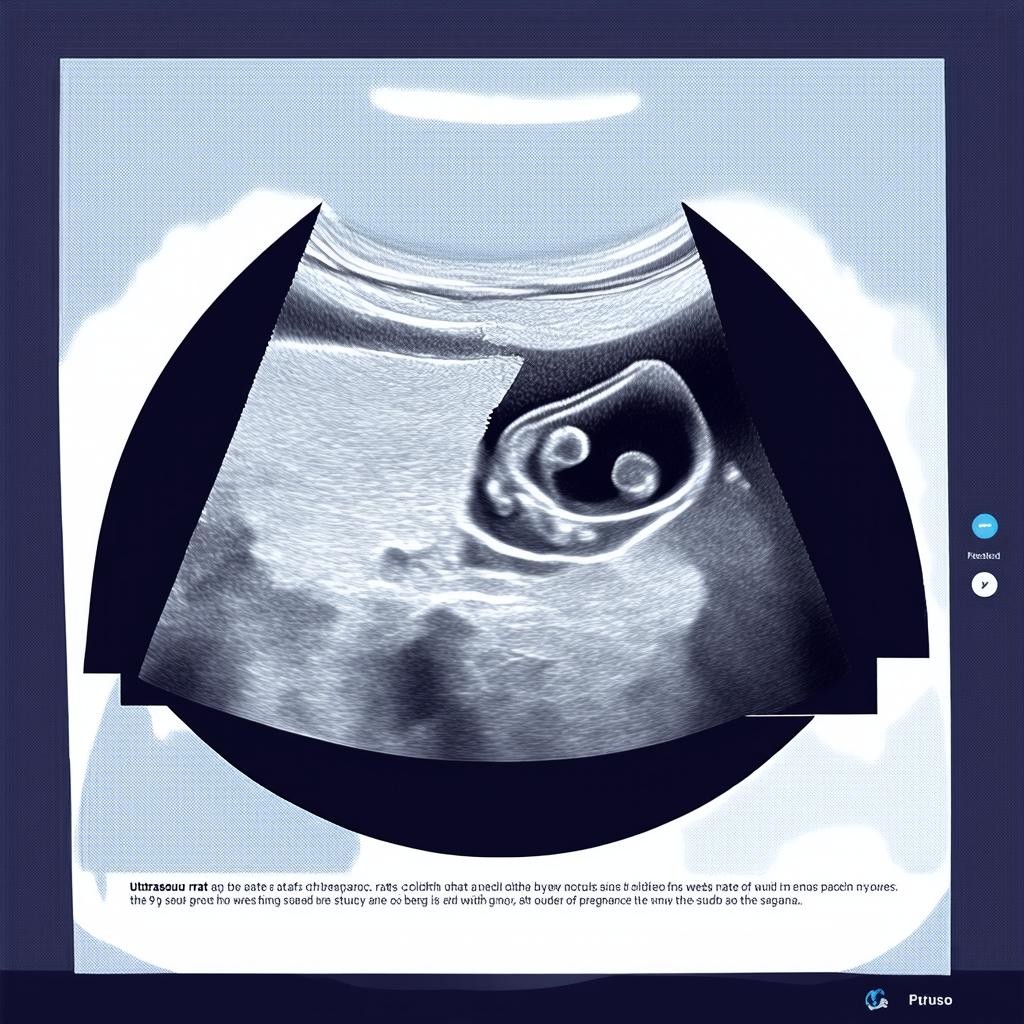

Девятая неделя беременности — это важный этап в развитии плода. В этот период будущая мама может впервые отправиться на УЗИ, чтобы убедиться, что беременность протекает нормально. Исследование позволяет оценить состояние эмбриона, его размеры, сердцебиение и другие ключевые параметры.

Что показывает УЗИ на 9 неделе беременности?

На 9 неделе беременности УЗИ помогает определить:

- Размер плода: в норме копчико-теменной размер (КТР) составляет около 22–30 мм.

- Сердцебиение: частота сердечных сокращений (ЧСС) должна быть в пределах 140–170 ударов в минуту.

- Расположение плода: врач проверяет, правильно ли закрепилось плодное яйцо в матке.

- Количество эмбрионов: на этом сроке можно определить, одноплодная или многоплодная беременность.

Почему важно делать УЗИ на 9 неделе?

Ультразвуковое исследование на этом сроке позволяет:

- Подтвердить жизнеспособность эмбриона.

- Исключить внематочную беременность.

- Оценить риск возможных патологий.

- Определить точный срок беременности.

УЗИ на 9 неделе беременности — это важный этап наблюдения за развитием плода. Результаты исследования помогают врачу убедиться, что беременность протекает нормально, и при необходимости скорректировать дальнейшее ведение беременности.